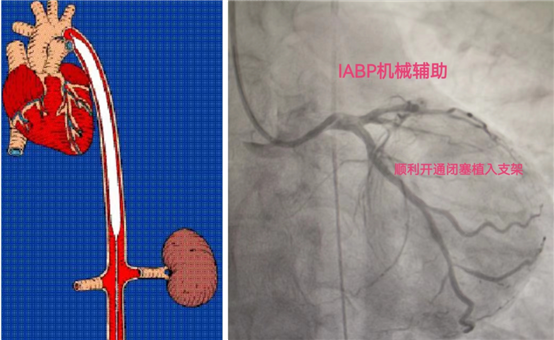

王前胜副主任医师分析患者病情、心电图表现以及冠脉造影结果后,快速做出手术策略及抢救预案:结合患者心电图表现,患者的罪犯血管为LCX,尽早开通LCX闭塞病变为首要目标!患者心源性休克状态,为避免手术过程中出现循环崩溃,对心脏进行机械循环支持,进而减轻心脏负荷,改善冠脉血供,尽快植入IABP(主动脉球囊反搏)球囊导管为第一要务!

在介入导管室护士和技师团队的默契协助下,迅速植入了IABP球囊导管进行循环支持,之后指引导管到位、导丝迅速通过闭塞处到达LCX远段,预处理后植入一枚支架,后扩球囊对支架优化处理,LCX闭塞病变终于恢复了TIMI-3级血流,整个手术过程用时仅一小时左右。术后患者的胸痛、胸闷症状明显缓解,生命体征平稳,患者的生命也从鬼门关被拉了回来,大家紧张的心终于恢复平静。